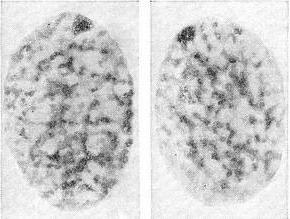

Статевий хроматин - особливі хроматиновые тільця клітинних ядер особин жіночої статі у людини та інших ссавців. Розташовуються біля ядерної оболонки, на препаратах зазвичай мають трикутну або овальну форму; розмір 0,7-1,2 мк (рис. 1). Статевий хроматин утворений однією з Х-хромосомах жіночого каріотипу і може бути виявлений у будь-якої тканини людини (в клітинах слизових оболонок, шкіри, крові, биопсированной тканини), Найбільш простим дослідженням статевого хроматину є дослідження його в клітинах епітелію слизової оболонки порожнини рота. Взятий шпателем зішкріб зі слизової оболонки щоки поміщають на предметне скло, фарбують ацетоорсеином і аналізують під мікроскопом 100 светлоокрашенных клітинних ядер, підраховуючи, скільки з них містять статевий хроматин. В нормі він зустрічається в середньому на 30-40% ядер у жінок і не виявляється у чоловіків (рис. 2).

![]() Рис. 1. Ядра, що містять статевий хроматин (зішкріб зі слизової оболонки порожнини рота здорової жінки). |

![]() Рис. 2. Ядро, яке не містить статевий хроматин (зішкріб зі слизової оболонки порожнини рота здорового чоловіка). Рис. 3. Ядро, що містить подвійний статевий хроматин (зішкріб зі слизової оболонки порожнини рота хворої трисомією X). |

В умовах патології можуть бути змінені розміри тілець статевого хроматину, а також їх число в кожному окремому ядрі і в середньому на 100 ядер. Статевий хроматин вивчають при цитологічному визначенні статі (наприклад, при гермафродитизм); для виявлення хромосомних хвороб (синдром Шерешевського - Тернера, для якого характерна відсутність статевого хроматину в жінок; синдром Клайнфелтера, при якому у чоловіків виявляють статевий хроматин; синдром трисомії X, при якому в ядрі замість одного тільце статевого хроматину виявляють два) (рис. 3); при ряді патологічних процесів, особливо злоякісних (зокрема, для вирішення питання про вид гормональної терапії при раку молочної залози); для характеристики дії низки фармакологічних засобів (наприклад, кортикостероїдів - щодо зміни ними кількості клітин, що містять статевий хроматин) та ін.